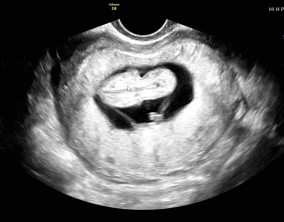

심장소리 이후, 함께 웃게 된 임밍아웃

유정원장님 치료 과정 내내 항상 따뜻하게 진료해 주셔서 감사한 마음이 큽니다. 덕분에 불안한 순간에도 마음을 다잡고 치료를 이어갈 수 있었습니다.